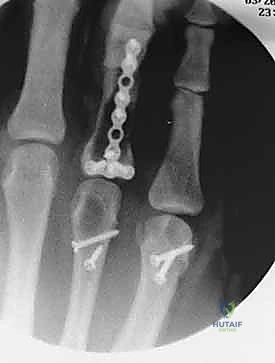

2. التثبيت الداخلي بالصفائح والبراغي المصغرة (Mini-Plates & Screws)

في حالات الكسور المتفتتة (Comminuted) أو الكسور الحلزونية الطويلة التي تميل للانزلاق، يلجأ الدكتور هطيف إلى التثبيت الداخلي المفتوح (ORIF). يتم استخدام صفائح معدنية دقيقة جداً (مصنوعة من التيتانيوم) تتناسب مع حجم عظام اليد.

* الميزة: تثبيت صلب وقوي جداً (Rigid Fixation)، مما يسمح للمريض ببدء العلاج الطبيعي وتحريك أصابعه في اليوم التالي للعملية، وهو أمر بالغ الأهمية لمنع تيبس الأوتار.

معرض الصور الشعاعية: تقييم النتائج الجراحية (Post-Op X-rays)

النجاح الحقيقي يُقاس بالاستعادة المثالية للشكل التشريحي للعظم. توضح هذه الصور الشعاعية بعد الجراحة الدقة المتناهية في إعادة محاذاة العظام وتثبيتها.

التثبيت المحكم يسمح بالشفاء العظمي الأولي (Primary Bone Healing) دون تكوين كتلة عظمية كبيرة (Callus) قد تعيق حركة الأوتار المنزلقة فوقها.